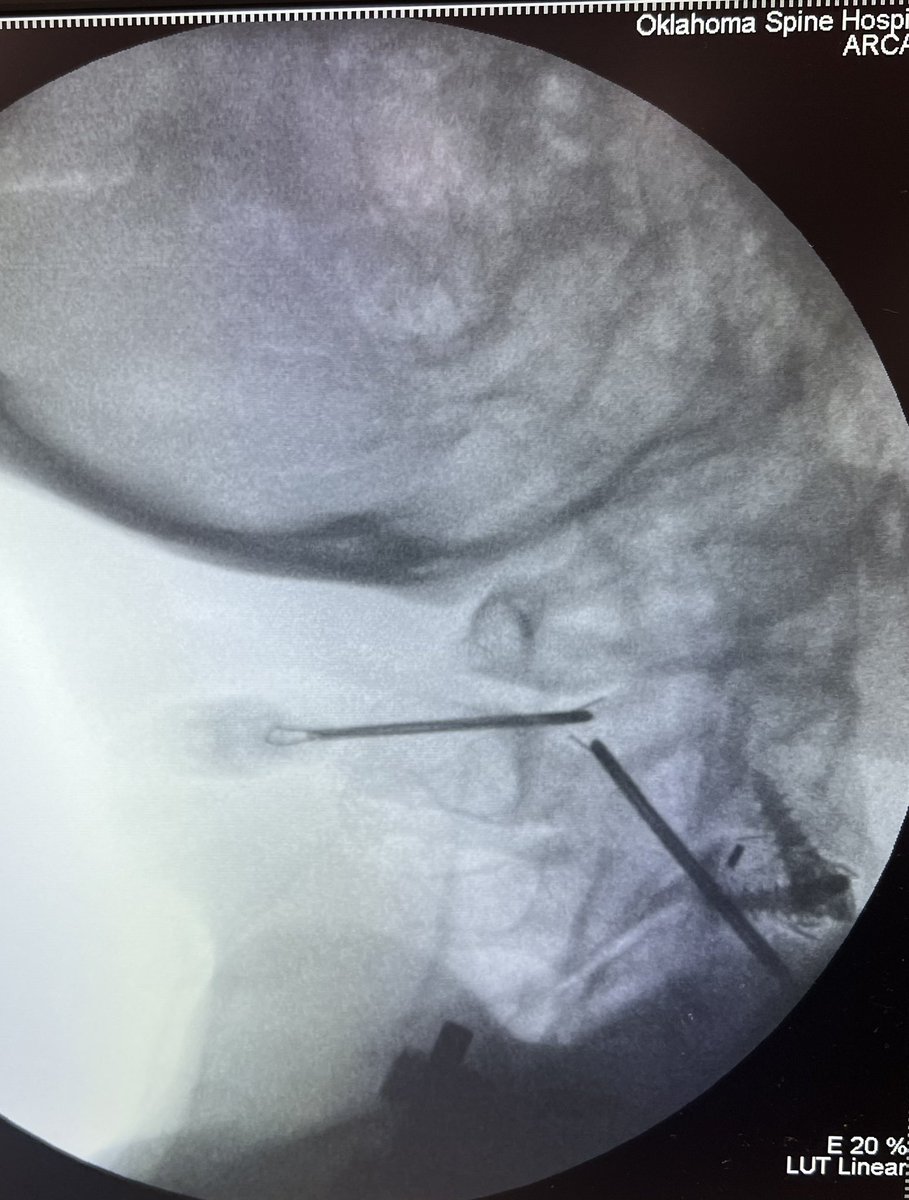

@TheStrykerIVS makes a great product, #SpineJack, that shows up in a lot of cool posts on this and other platforms.

This example was just posted by @neuroradiology - a great example of the genre.